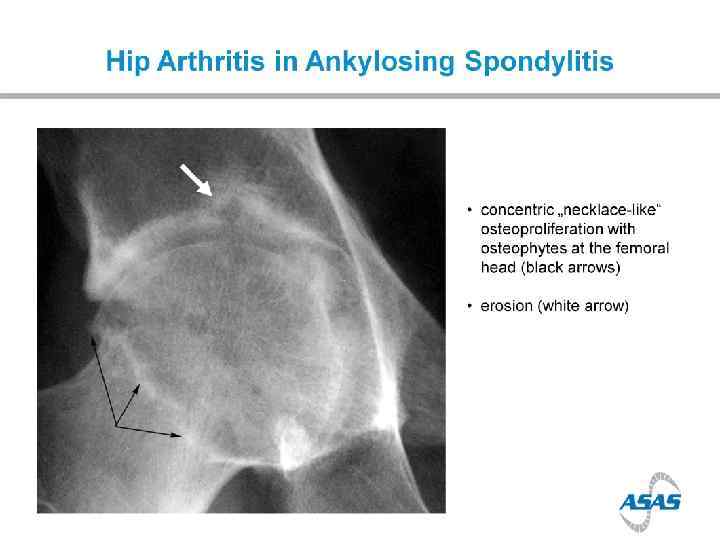

Arthritis